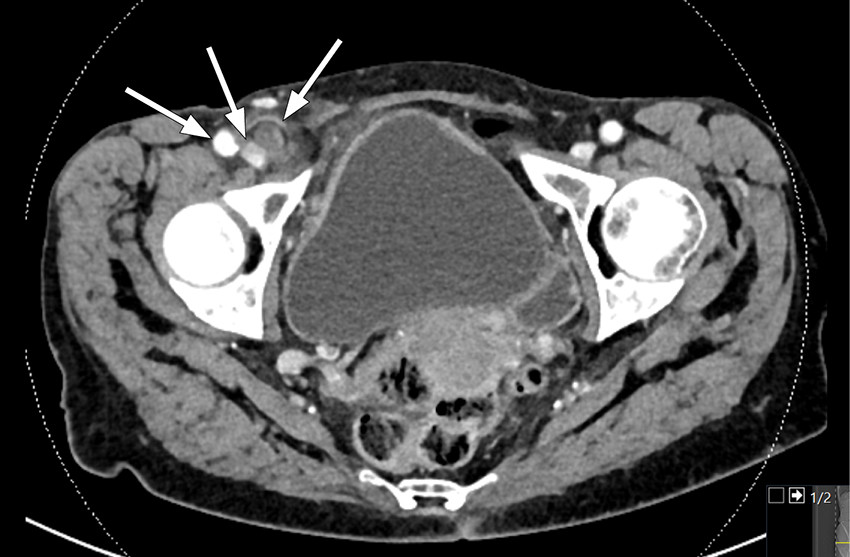

Figure 2 Sagittal CT scan. The arrow shows a mass in the inguinal canal with a small gas bubble.

On account of suspected appendicitis, CT abdomen with contrast was performed and revealed a superficial tubular structure in the right fossa with adjacent adipose tissue remodelling, including thickening of the peritoneum behind. The scan was interpreted as showing an inflamed appendix; the wall of the appendix was also somewhat poorly defined in places, suggesting perforated appendicitis. In addition, a mass was seen in the right inguinal canal with a small gas bubble. Although there was no definite communication with the appendix, it was nevertheless likely that the appendix had herniated into the femoral canal.

The condition is often diagnosed during surgery, but can be detected pre-operatively on CT abdomen. CT is the best modality for visualising de Garengeot's hernia as it can reveal the location and contents of the hernia. The femoral canal is medial to the femoral vein and posterior to the inguinal ligament (1, 4).